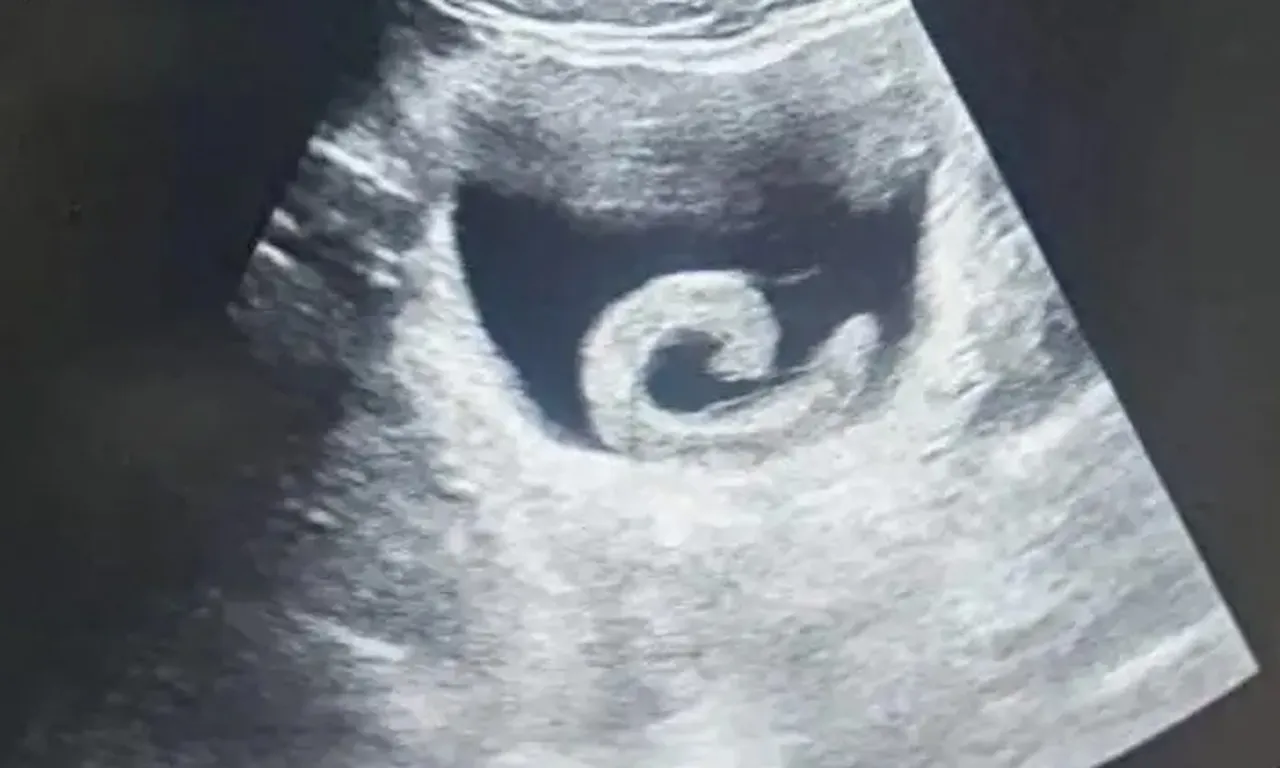

ULTRASONDA ŞOKE EDEN GÖRÜNTÜ

Ağrılar dayanılmaz hale gelince genç, yerel bir hastaneye başvurmak zorunda kaldı. Doktorlar, hastanın açıklamaları karşısında şaşkına döndü ve yapılan ultrason muayenesi mesanede canlı bir sülüğün bulunduğunu ortaya koydu.